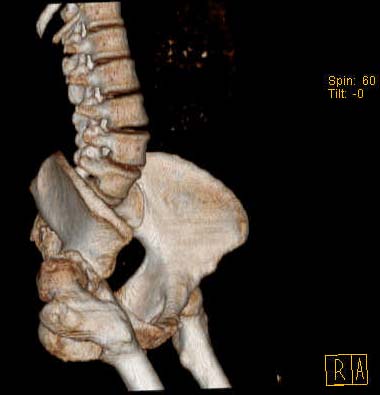

Уважаемые коллеги!Женщина, 35 летВ прошлом по поводу врожденного вывиха бедра перенесла операцию остеотомии по Шанцу

с удлинением правой ноги за счет бедра на уровне диафиза. В последнее время прогрессируют боли в правом тазобедренном суставе, порочное положение правой ноги, затруднена ходьба.Вопросы:1) Целесообразно ли эндопротезирование правого тазобедренного сустава?2) Целесообразный ли следующие действия: канал бедренной кости предполагаем вскрыть для введения ножки протеза на высоте угловой деформации, предполагаем низведение большого вертела с мышцами; протез будет подобран индивидуально, предполагается умеренная версия?В приложении рентгенограммы и трехмерная КТ.В цветном и более качественном варианте КТ размещена здесь